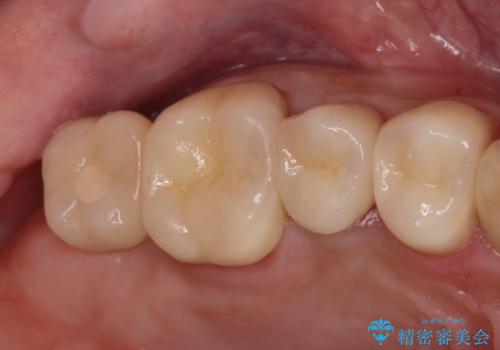

適合の良い被せ物、インプラントが入りました。

全ての治療が終わった後はNG(ナイトガード)を使用し、定期的にメンテナンスに

くることをお勧めしたいます。